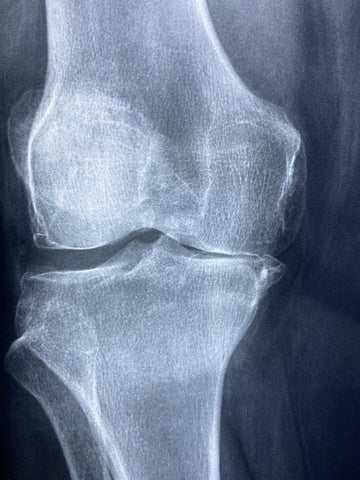

Arthritis is one of the leading causes of disability, affecting over 40 million people in the U.S. alone, with osteoarthritis being the most common form. By 2020, this number was projected to reach 60 million. While medication can provide temporary relief, studies show that cycling offers a natural, long-term solution for managing and even preventing arthritis symptoms.